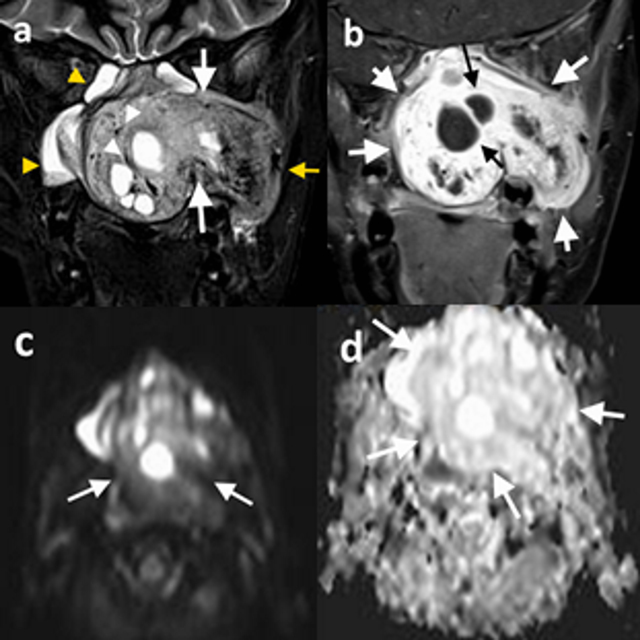

Figure 1

13-year-old male patient (patient 5), (a) coronal T2-weighted precontrast, (b) coronal T1-weighted postcontrast, (c) DWI, and (d) ADC map demonstrate a left-sided nasopharyngeal mass which enlarges the ipsilateral pterygopalatine fossa (a, white arrows) and extends into the temporal fossa (a, yellow arrow). The mass is hyperintense on T2-weighted image (a) and exhibits significant contrast enhancement (b). Diffusion-weighted images (c) showed no diffusion restriction, and the lesion has high signal intensity on the ADC map (d). The tumor demonstrates internal cystic components (b, black arrows) and signal-void regions (a, white arrowheads). Image a demonstrates inflammatory signal changes in maxillary and sphenoid sinuses (yellow arrowheads).

MRI signal intensity of the tumors were heterogeneous in all cases. Tumors were largely isointense to muscle on T1-weighted images and hyperintense on T2-weighted images. All lesions had internal signal-void regions, and all exhibited intense enhancement after intravenous (IV) contrast injection. In four patients for whom the diffusion-weighted images were available, diffusion restriction was not an associated feature (Figure 1). ADC values for these tumors were high, with a mean value of 1.6 ×10–3 mm2/s, consistent with benign lesions.

On MR images, JNA demonstrates low signal-intensity on precontrast T1-weighted sequences and medium- to high-signal intensity on T2-weighted sequences [1]. However, most of the cases in our series showed isointensity to muscle on T1-weighted images, and one case exhibited high-signal intensity. On T2-weighted images, the tumors were of isohyperintense signal. Intratumoral signal voids and intense enhancement of the tumor after IV contrast injection are characteristic MRI features of JNA, and we observed these findings in all of our patients. None of the lesions in this study demonstrated diffusion restriction on DW images, and their mean ADC values were high, as expected in hypocellular benign tumors. The lesions’ lateral extensions were appreciated better from axial and coronal images, while the evaluation of the superior extensions of the tumors were easier using the sagittal and coronal images [113]. Although the presence of intratumoral degenerative cystic components is a rare radiological finding of JNA, we observed this feature in four out of six patients (Figure 1).